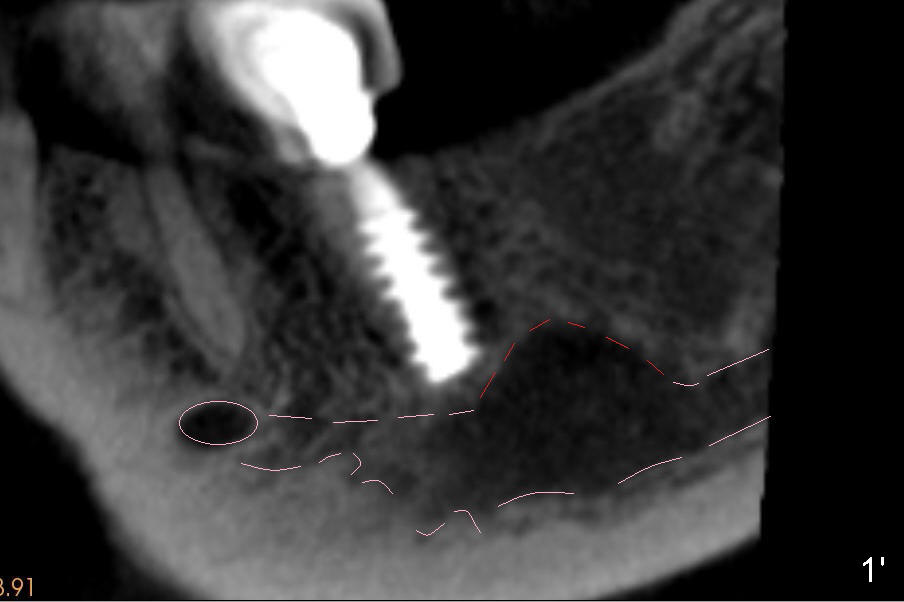

Abnormal anatomy of IAN is found (Fig.1' (sagittal section 200 µm): pink outline) at the site of #18 of a 56-year-old lady. There is an extra superior (coronal) bulging segment (Fig.1' red dashed line).